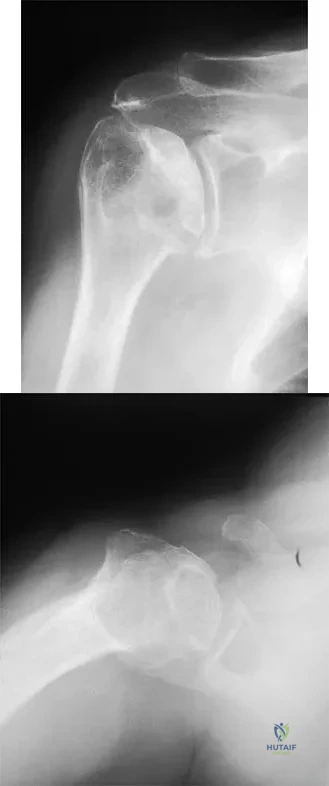

Question 13

A 58-year-old woman with a history of severe asthma and long-term prednisone use reports a progression of chronic shoulder pain for the past 6 months. Radiographs and MRI scans are shown in Figures 30a through 30d. What is the most likely diagnosis?

Explanation